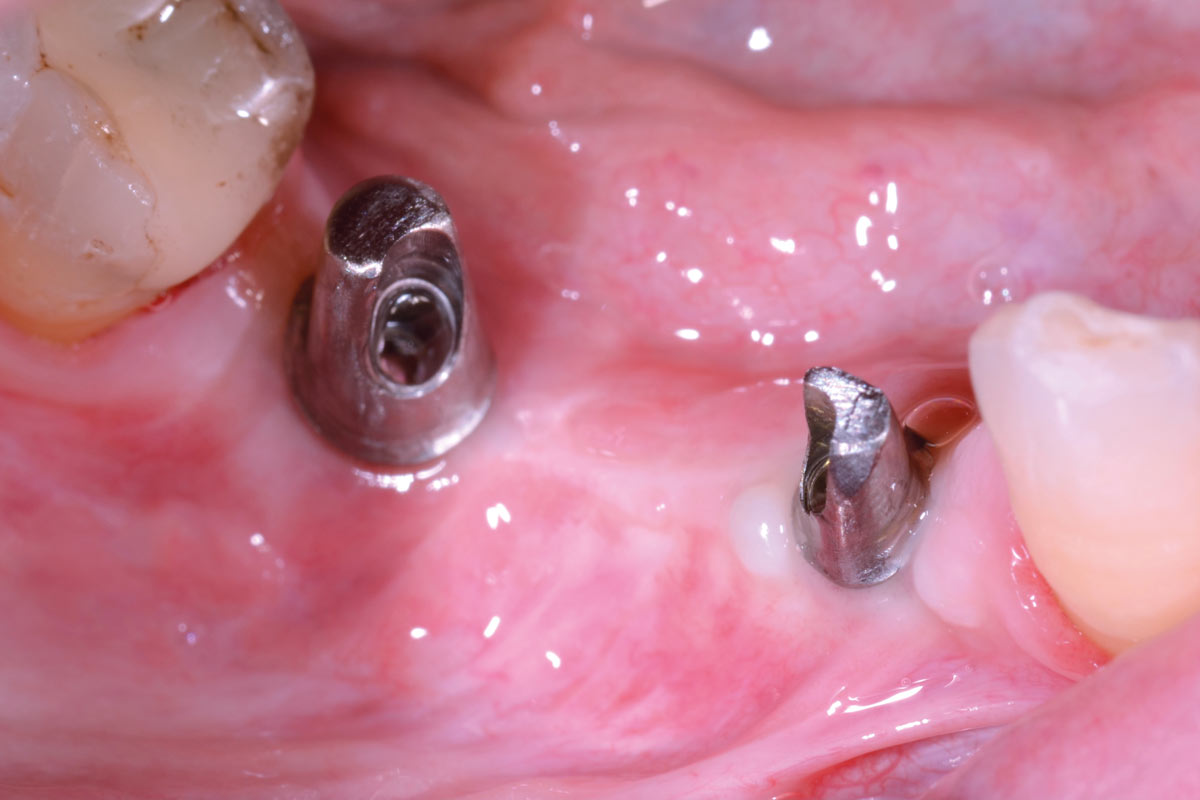

22/29 - Clinical view after insertion of the healing abutmentVertical bone augmentation and broadening of attached gingiva using cerabone®, permamem® and mucoderm® - Dr. R. Naimoli